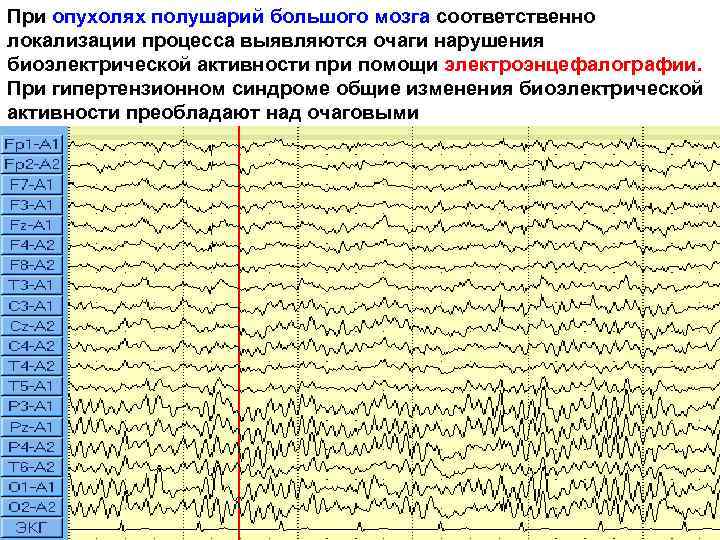

При опухолях полушарий большого мозга соответственно локализации процесса выявляются очаги нарушения биоэлектрической активности при помощи электроэнцефалографии. При гипертензионном синдроме общие изменения биоэлектрической активности преобладают над очаговыми 16